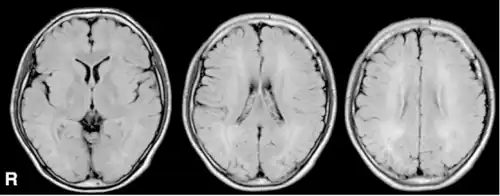

| MRI, FLAIR -diffuse signal increase of deep white matter. | |